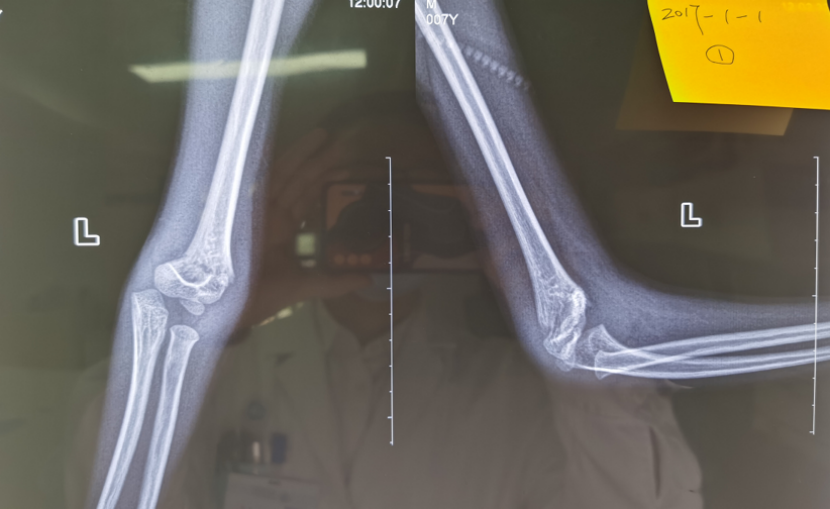

病例1:小明(化名)、男、12岁,8年前因摔伤致“左肱骨髁上骨折”,于外院行手术治疗,手术后逐渐发生左肘内翻畸形。

受伤当时的X线片